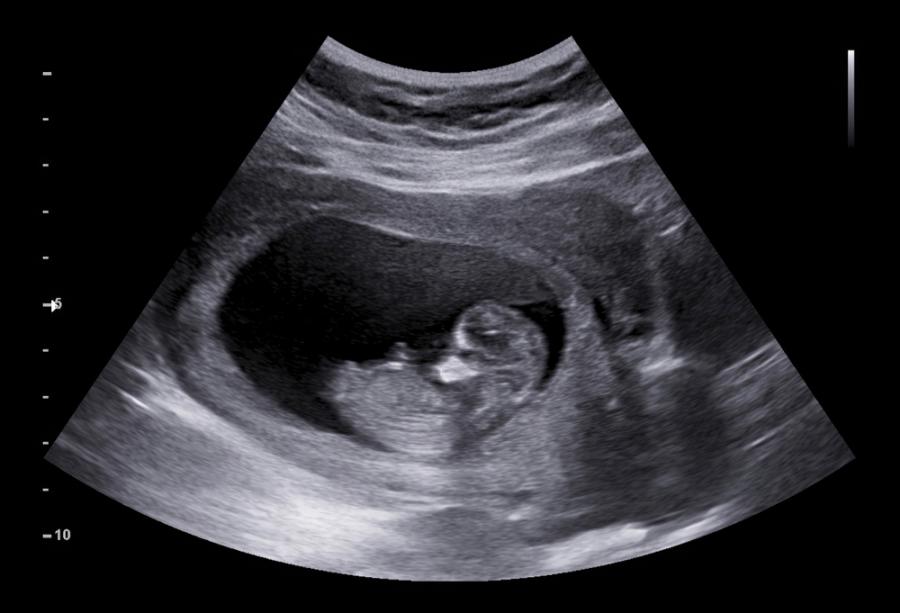

Състоянието е изключително трудно за откриване и обикновено се диагностицира чрез ултразвук или на базата на начина, по който са протекли миналите бременности на жената (ако има такива). Така например ако тя вече е раждала чрез цезарово сечение, то рискът да развие тази аномалия е много по-висок (същото важи и ако е имала плацента превия, при която плацентата покрива частично или напълно маточната шийка). Въпреки това ултразвукът е скъп, а способността да се диагностицира PAS зависи до голяма степен от нивото на опит на човека, извършващ сонографията.